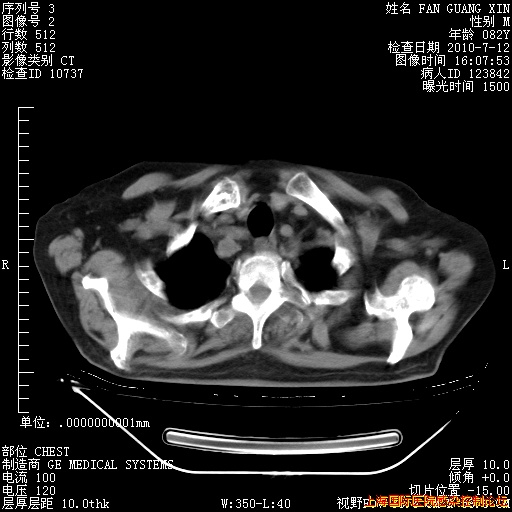

今天复查CT

今天CT

整整相隔30天的肺部CT好像有所好转啊。甲强龙减量第3天,需要观察体温。

海管,自昨日你和我通完话后,不知您岳父消化道症状有无缓解?体温怎样?阅读7.12日胸部ct,个人认为目前激素治疗是有效的,甲强龙减量是适宜的。因在抗痨治疗,需密切观察肝功、肾功能和血常规。不过,老年、长期住院和大量使用激素,很担心菌群失调发生